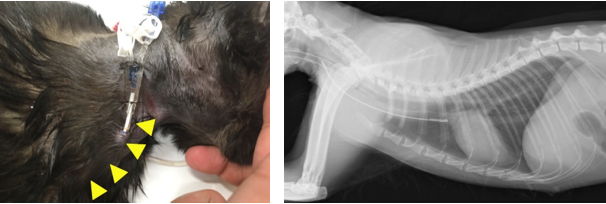

首の静脈にカテーテルを挿入してここから脱血、返血を行います。

症例は柴犬、1歳11ヶ月、未避妊雌、体重4.5kgで食欲不振および水様性下痢を主訴に紹介元病院を来院しました。入院下で治療行っていたのですが、3日目から尿が出なくなり、腎数値の上昇が見られたため、その日のうちに当院に紹介がありました。

7回目の血液透析を終えた後から腎数値は透析を行わずに下がり始めました。その後は21日目に透析カテーテルの抜去を行い、食事療法のみで管理しました。